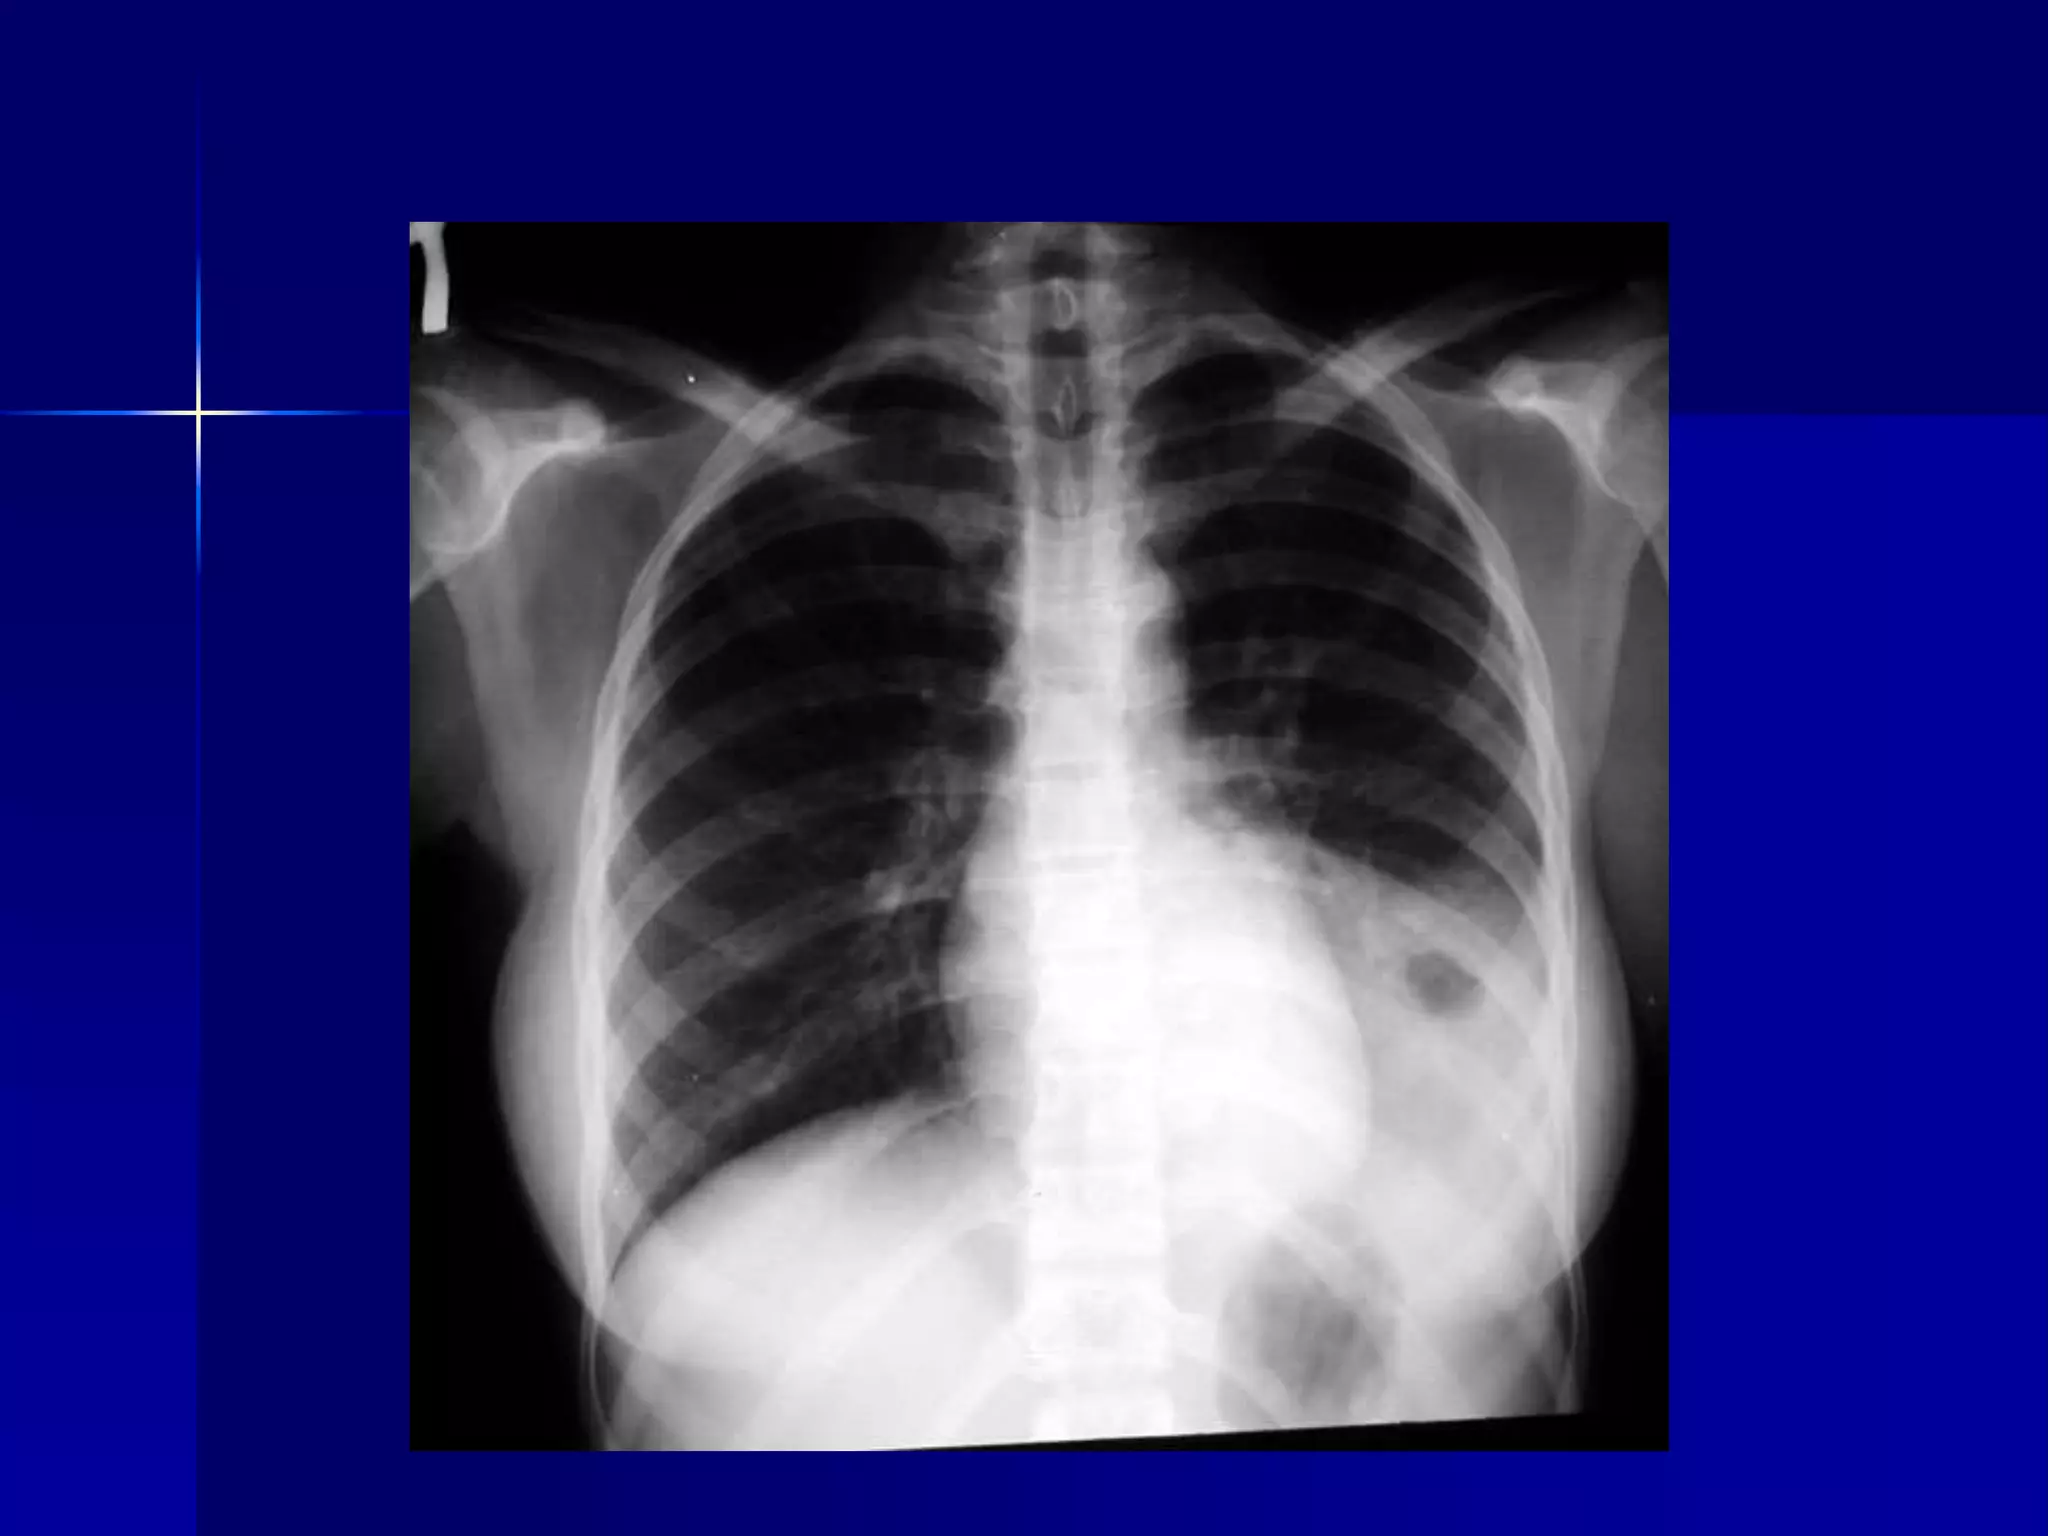

 Massive Pleural Effusion

 Atelectasis Right Lung

 Massive Massive Pleural Effusion